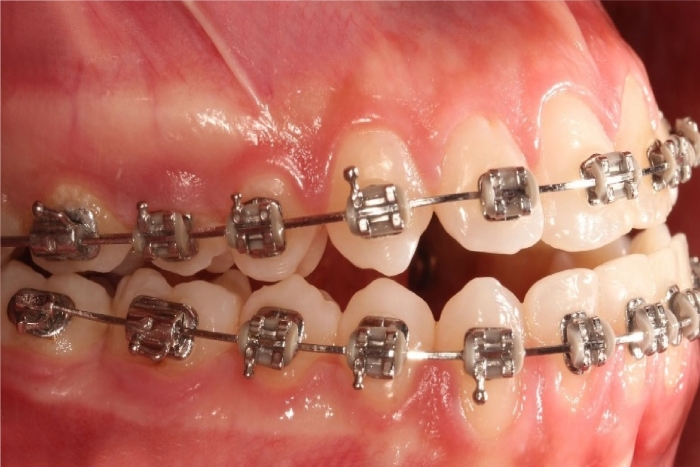

Oclusão após a cirurgia